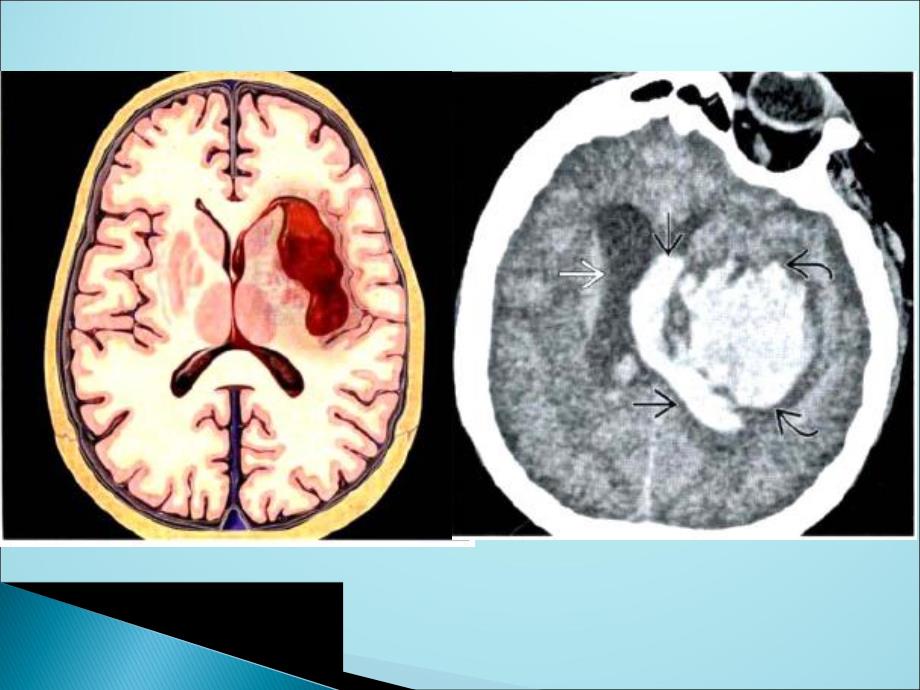

1、继发于系统性高血压(Hypertension,HTN)的急性非创伤性ICH纹状体内囊血肿:壳核或外囊占60%65%丘脑出血:1525%桥脑、小脑占:10%多灶性“微出血”1%5%如果有凝血功能障碍或活动性出血,则病灶密度不均匀。其他表现:出血破入脑室 占位效应:脑积水、脑疝超急性期(6Hs):T1等/低,T2高信号急性期(7Hs3Ds):T1等/高,T2低信号亚急性期(出血后数天):T1高,T2低-高信号慢性期(出血后数周数月):T1高,T2低信号1020%卒中病人为hICH50%非创伤性ICHS由hICH引起高血压病是4570岁病人自发性ICH的常见原因T1WI C+T2WIT2*GREMI

2、P SWI诊断要点 高血压病人壳核、外囊或丘脑的圆形或卵圆形高密度肿块。NECT 圆形或或卵圆形高密度脑实质肿块。若存在凝血功能障碍或活动性出血,则病灶密度不均匀 其他表现 出血破入脑室 占位效应:脑积水、脑疝CECT 急性期无增强超急性期(6Hs):T1等/低,T2高信号急性期(7Hs3Ds):T1等/高,T2低信号亚急性期(出血后数天):T1高,T2低-高信号慢性期(出血后数周数月):T1高,T2低信号多发低信号病变(黑点)见于长期高血压病人亦常见于脑淀粉样血管病血管畸形 通常年轻人血压正常,常见于海绵状血管瘤药物滥用(尤其是年轻人)可卡因可引起突发血压增高深部静脉血栓形成 可能有脱水、感冒、妊娠/口服避孕药病史出血性肿瘤 继发性和原发性肿瘤淀粉样血管病(多发性微出血)脑叶出血基底节 通常为老年人,血压正常。谢谢大家!